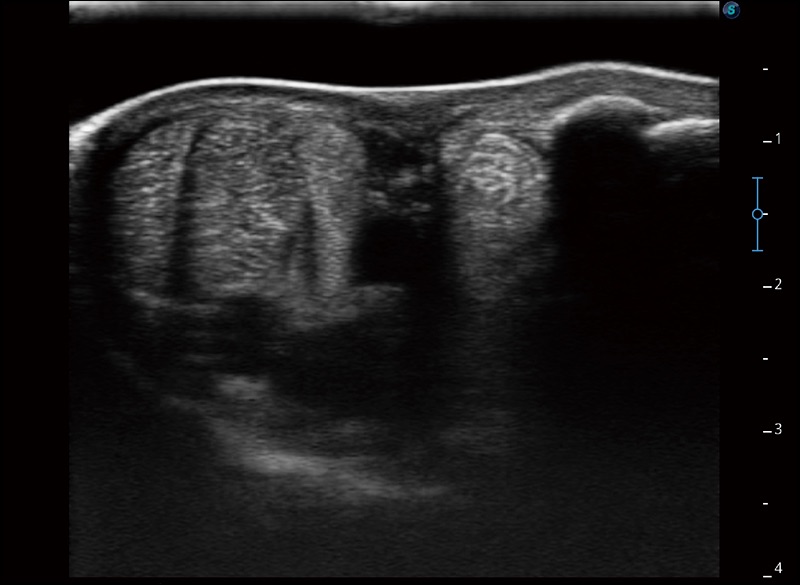

α1卓越的图像质量和便捷的工作流程,使每位宠物医生都能轻松扫查。其全面的兽用应用功能和紧凑型的结构设计,可以满足动物检查的多种需要。专业的预设检查模式和多领域测量软件包有助于为不同类型的动物提供检查, 让宠物医生能够出色的完成工作。

扩展成像

支持线阵和凸阵探头,一键操作即可获得更宽的图像视野

实时宽景成像

可实时观察感兴趣区域和病变位置